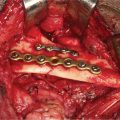

Isolated orbital floor fractures (blowouts) are often the result of impact injury to the globe resulting in a sudden increase in intraorbital hydraulic pressure. This kinetic energy is transmitted in an inferior and medial vector to the orbital floor (hydraulic theory) (Figure 13.1). Alternatively, the posterior transmission of a direct blow to the infraorbital rim causes buckling and resultant fracture of the orbital floor (buckling theory) (Figure 13.2). Fractures of the orbital floor can increase the volume of the orbit with resultant enophthalmos and hypoglobus. These can be highlighted on preoperative (Figure 13.3a–c) and postoperative (Figure 13.4a–c) computed tomographic (CT) scan imaging. In addition, the inferior rectus or periorbital soft tissue can become entrapped within the fracture line, resulting in restriction of extraocular eye movements. Table 13.1 indicates the special equipment used to surgically manage this injury.